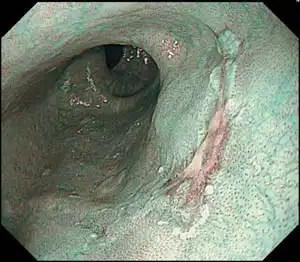

EVIS LUCERA ELITE的NBI提供了EVIS LUCERA SPECTRUM可视距离的两倍。NBI的性能大大提高打开了令人兴奋的新临床应用,并强化了NBI作为胃镜检查标准的地位。